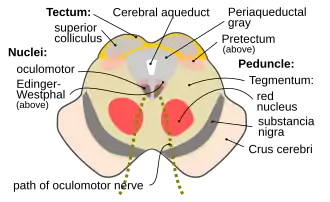

Cross section of the midbrain at the level of the superior colliculus showing oculomotor nucleus .

Cross section of the midbrain at the level of the superior colliculus showing oculomotor nucleus . Scheme showing central connections of the optic nerves and optic tracts.